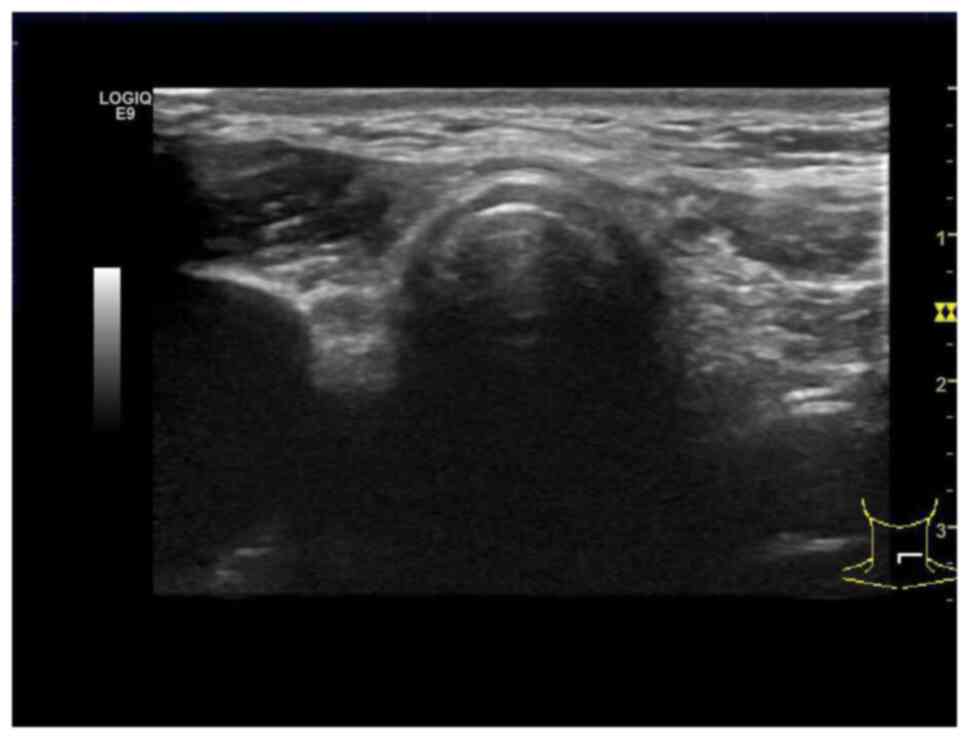

Serum calcitonin and CEA levels dropped to normal 1 week after the surgery (Table I). Replacement therapy with L-thyroxine (100 µg/per day; lifetime) was performed at a TSH level of 0.5-5.5 µU/ml. TSH, calcitonin and CEA were detected every 3 months and follow-up ultrasound was performed every 3 months. The latest follow-up was performed in May 2024. Ultrasound showed no suspicious lymph nodes or recurrent lesions (Fig. 5). Laboratory tests illustrated a TSH level of 3.1 µU/ml, a serum calcitonin level of 2.9 pg/l and a CEA level of 2.5 ng/l.

Figure 5

Ultrasonography showing no recurrent lesion or suspicious lymph node.